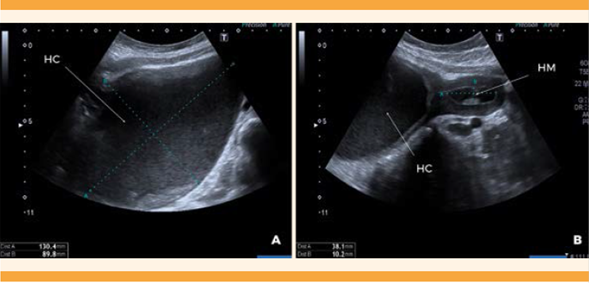

Por ecografía se confirmó la existencia de un globo vesical que ameritó sondaje uretral que resultó efectivo (se evacuaron 1200 mL de orina clara) antes de continuar con la exploración, esto disminuyó el dolor. Enseguida, mediante ecografía transabdominal, se visualizó la vagina distendida y ocupada por contenido homogéneo e hipoecoico de 130 x 89 mm (hematocolpos). El cuello uterino se encontró ligeramente entreabierto, y el útero aumentado de tamaño consecuencia de la ocupación de la cavidad por contenido de características similares, de 38 x 10 mm (hematometra). Figura 1

Figura 1 Ecografía transabdominal, corte sagital. A. Hematocolpos (HC). B. Hematocolpos (HC) y hematometra (HM).